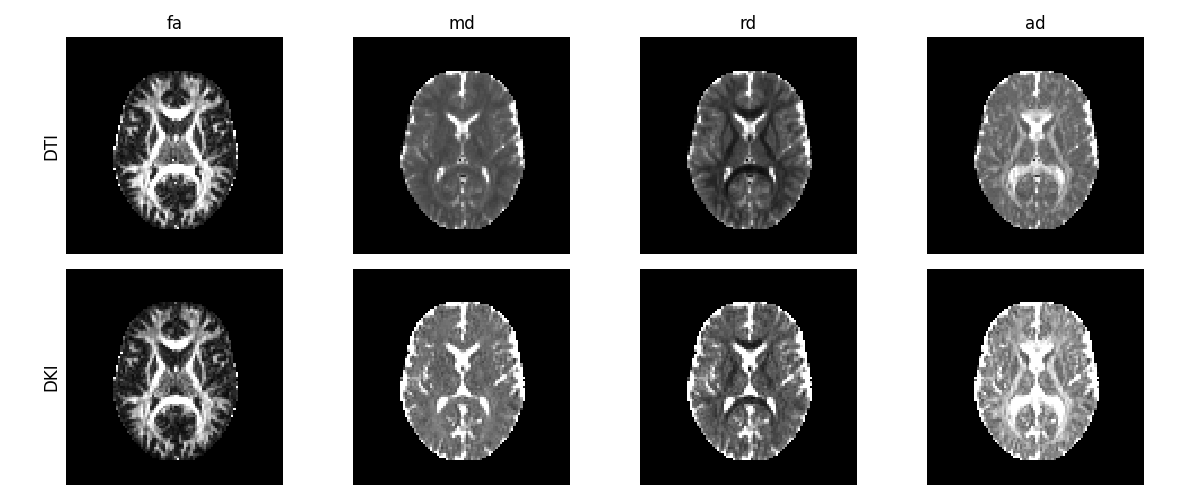

The fit method creates a DiffusionKurtosisFit object, which contains all the

diffusion and kurtosis fitting parameters and other DKI attributes. For

instance, since the diffusion kurtosis model estimates the diffusion tensor,

all standard diffusion tensor statistics can be computed from the

DiffusionKurtosisFit instance. For example, we can extract the fractional

anisotropy (FA), the mean diffusivity (MD), the radial diffusivity (RD) and

the axial diffusivity (AD) from the DiffusionKurtosisiFit instance. Of

course, these measures can also be computed from DIPY’s TensorModel fit,

and should be analogous; however, theoretically, the diffusion statistics

from the kurtosis model are expected to have better accuracy, since DKI’s

diffusion tensor are decoupled from higher order terms effects

[9], [2]. Below we compare

the FA, MD, AD, and RD, computed from both DTI and DKI.

Diffusion tensor measures obtained from the diffusion tensor estimated from DKI (upper panels) and DTI (lower panels).

DTI’s diffusion estimates present lower values than DKI’s estimates, showing that DTI’s diffusion measurements are underestimated by higher order effects (for detailed discussion on this see [2].